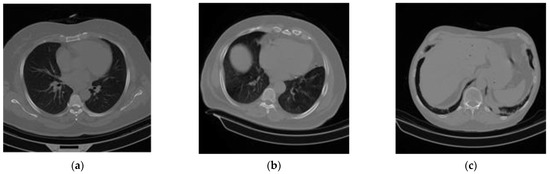

This section describes the datasets considered for this research. To ensure comparable accuracy and rapidity in the screening and testing of COVID-19, the use of CT scans is satisfactory. In this paper, a large dataset of COVID-19, normal or non-COVID-19, and community-acquired pneumonia (CAP)-affected lung CT scan axial slices (along with their corresponding metadata) was built by curating data from [23,27,28,37,48,49,50,51,52]. As an example, curated images from each of the seven datasets are shown in Figure 1.

Figure 1.

A sample of the experimental CT scan dataset: (a) normal or non-COVID-19, (b) COVID-19, and (c) community-acquired pneumonia (CAP).